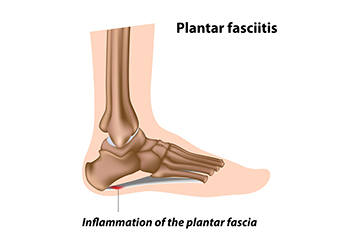

Heel pain is often associated with plantar fasciitis. The plantar fascia is a band of tissues that extends along the bottom of the foot. A rip or tear in this ligament can cause inflammation of the tissue.

One condition is plantar fasciitis. Plantar fasciitis is caused by the inflammation of the plantar fascia, or the band of tissue that connects the heel bone to the base of the toes. The pain from this condition is initially mild but can intensify as more steps are taken when you wake up in the morning. To treat this condition, medication will likely be necessary. Plantar fasciitis is often associated with heel spurs; both require rest and special stretching exercises.

Plantar Fasciitis and Podiatry Care

Plantar fasciitis is caused by inflammation of the plantar fascia, the thick band of tissue that runs along the bottom of the foot and supports the arch. This condition often leads to sharp heel pain, especially with the first steps in the morning or after long periods of rest. Risk factors include prolonged standing, flat feet, high arches, obesity, and wearing footwear that lacks proper support. Symptoms include aching, stiffness, or a burning sensation in the heel. If left untreated, the pain can become chronic and interfere with daily activities. A podiatrist can diagnose plantar fasciitis, provide targeted stretching exercises, and offer custom orthotics or treatments to relieve pain and promote healing. If you have heel pain, it is suggested that you consult a podiatrist who can accurately diagnose and treat the condition.

Plantar fasciitis is one of the most common causes of heel pain. The plantar fascia is a ligament that connects your heel to the front of your foot. When this ligament becomes inflamed, plantar fasciitis is the result. If you have plantar fasciitis you will have a stabbing pain that usually occurs with your first steps in the morning. As the day progresses and you walk around more, this pain will start to disappear, but it will return after long periods of standing or sitting.

The plantar fascia is a connective tissue in the heel that stretches across the bottom length of your foot. Plantar fasciitis occurs when the connective tissue becomes inflamed, causing heel pain and discomfort during physical activity. Although the condition is completely treatable, traditional methods can take up to a year to start becoming effective.

Plantar fasciitis is caused by a number of everyday activities, so understanding the condition is important for managing and treating it. One of the most common causes of plantar fasciitis is excessive running, especially with improper fitting or non-supportive shoes. Too much exercise can lead to the plantar fascia being overworked and overstretched, which can cause tears in the tissue. Along with improper fitting shoes, pronation, the rolling of the feet inward, is a common cause of plantar fasciitis. If not treated properly, the plantar fascia becomes overstretched and starts to tear, causing inflammation.